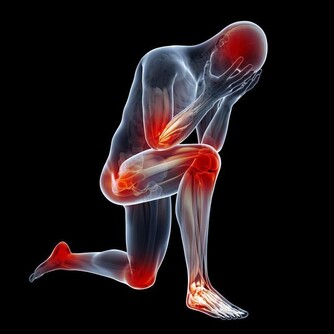

大部分肝癌患者到了晚期都會有很明顯的疼痛感,而早期很少有疼痛情況出現,一般出現明顯的疼痛都已發展到中晚期了,但是有疼痛并不代表就是肝癌,需要分清楚是哪裡疼痛,然後再進行針對性的檢查。

*****1.肝區疼痛*****

這是肝癌最典型的疼痛,位於右上腹,判斷是否有肝病病變一般主要看這個部位有沒有出現不適,也有肝病患者會出現上腹或下腹的疼痛,如果肝病發展到晚期,整個腹部都會有強烈的痛感。

*****2.肩部疼痛*****

如果是發生在右肩部,是屬於放射痛的範圍,肝癌患者會出現放射性的疼痛,不過膽囊疾病也可能會出現右肩部疼痛。

*****3.腰背部的疼痛*****

這種疼痛比較常見,在溫度發生變化或者勞累的情況下也會出現,一般進行合適的休息會自行緩解。而肝癌導致的腰背部的疼痛是因為受到腫瘤的壓迫,腫瘤壓迫神經、肌肉,從而出現腰背部疼痛的現象。

*****4.胸口處疼痛*****

胸口連著心臟,很多人會認為是心臟發生問題,其實胸口疼痛和肝癌也要一些關係,因為肝和心臟緊挨著,如果有肝癌可能會壓迫到周圍器官,也可能造成胸口處疼痛的情況出現。

*****5.胃痛*****

比如肝硬化會導致門靜脈高壓、門靜脈高壓又會導致胃底靜脈曲張,這樣就會導致胃粘膜血液循環變差,很容易引起糜爛、胃炎,因此也會導致胃痛。

*****6.轉移灶的疼痛*****

肝癌會轉移到其他部位,比如轉移到肺部、骨骼處、那麼就可能出現骨痛、胸痛的情況。

如果有肝癌與多部位的疼痛都有一定的關係,除了關注疼痛之外,還要及時了解肝癌的症狀以及相關檢查。